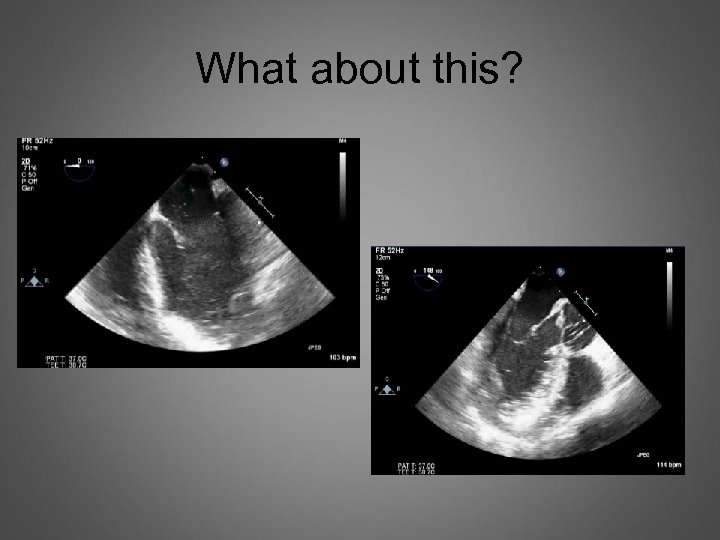

What about this?